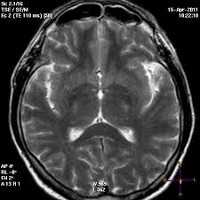

![Признаки энцефалопатии Вернике на снимке МРТ [22]](https://probolezny.ru/media/bolezny/encefalopatiya-vernike/priznaki-encefalopatii-vernike-na-snimke-mrt-22_s.jpg)

Может применяться компьютерная томография (КТ) и магнитно-резонансная томография (МРТ). С помощью КТ определяют участки пониженной плотности в центральном сером веществе среднего мозга и в части таламуса, но в большинстве случаев этот метод не выявляет очаговой патологии при острой энцефалопатии.

Наиболее эффективный метод диагностики энцефалопатии Вернике — это МРТ. Интерпретировать результаты МРТ сможет только врач.

В половине случаев синдром Гайе-Вернике сопровождается генерализованным замедлением волн при ЭЭГ. РЭГ зачастую определяет диффузное снижение церебрального кровотока. КТ головного мозга, как правило, не регистрирует патологические изменения в церебральных тканях. МРТ головного мозга позволяет выявить гиперинтенсивные области в медиальных ядрах таламуса, мамиллярных тельцах, стенках III желудочка, ретикулярной формации, сером веществе, окружающем сильвиев водопровод, крыше среднего мозга. Зоны поражения склонны накапливать контраст, вводимый при проведении дополнительного контрастирования в ходе МРТ. В перечисленных областях могут определяться петехиальные кровоизлияния и признаки цитотоксического отека.